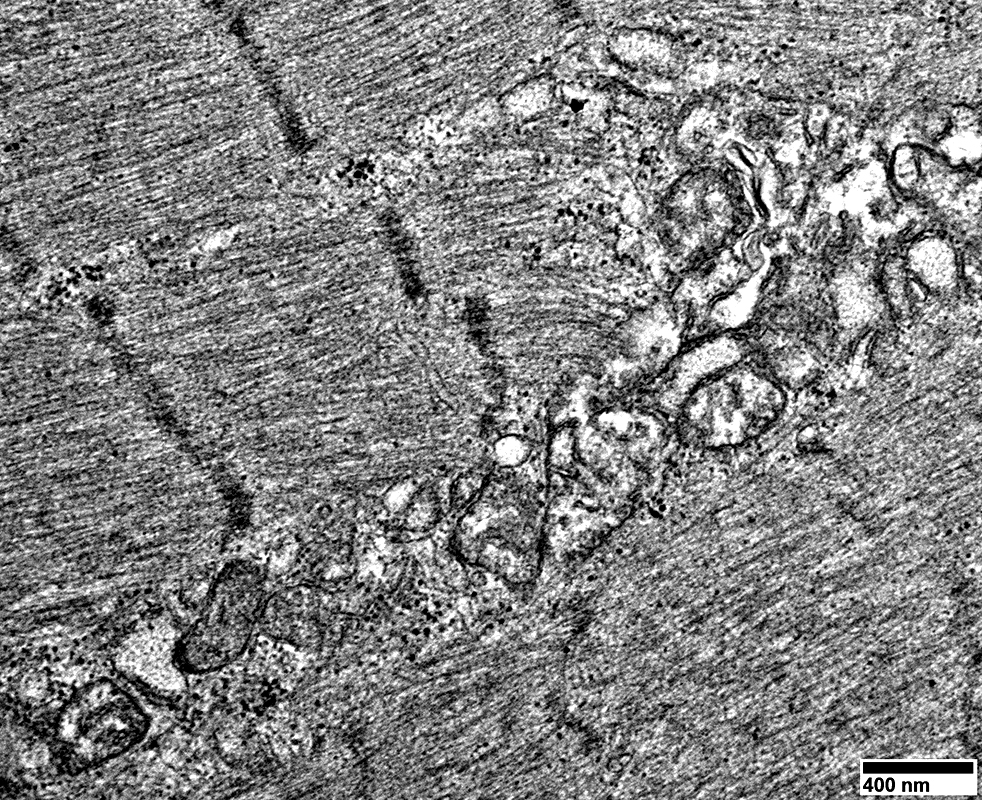

Mitochondrial proliferation between sarcomeres

From: R Schmidt

Mitochondrial proliferation & enlargement: Beneath muscle fiber surface